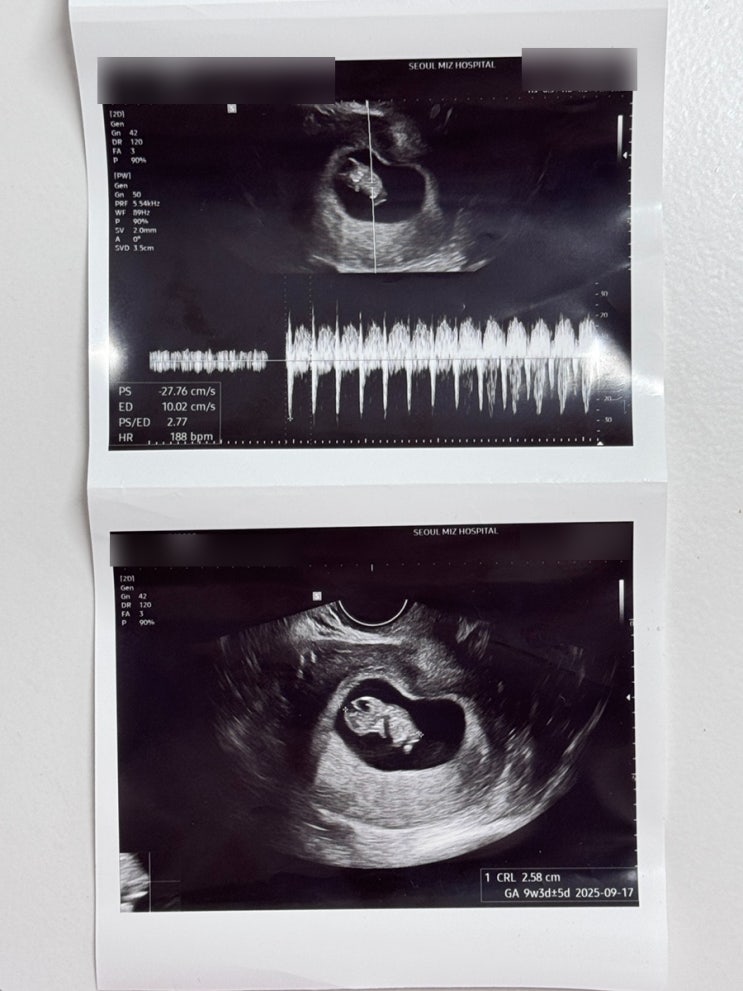

[임신일기] 9주차 초음파 젤리곰(?) 확인/ 임신초기검사 채혈

9주2일차 지난 7주차 병원 방문 후 2주를 또 잘 견뎌냈어요ㅎㅎ 정말 아직까지도 실감이 잘 안나고 잘 있나...